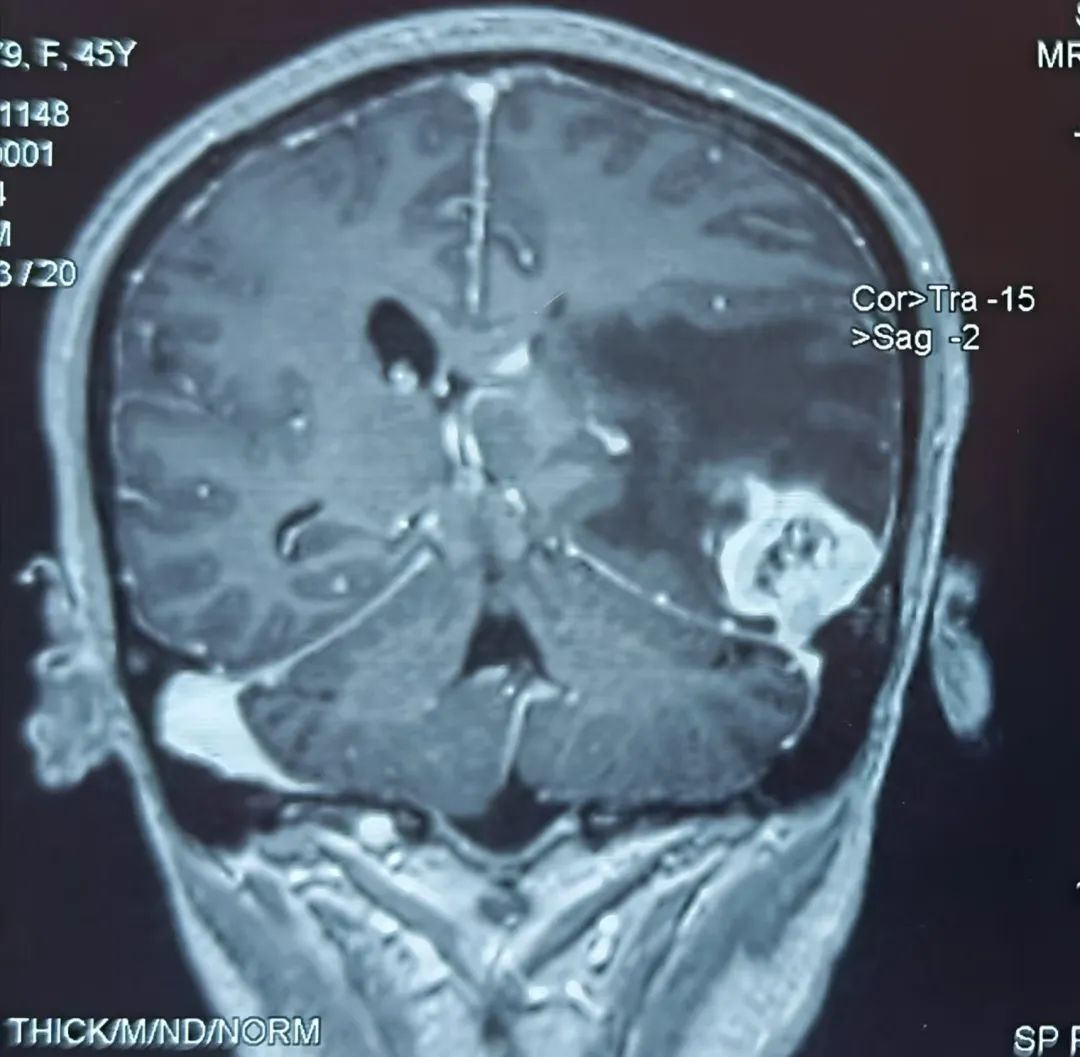

患者43岁,肾肿瘤术后一个半月开始出现头痛难忍,伴有恶心、呕吐、言语不流利,每天靠止痛药缓解头痛,到医院行头部核磁检查提示左颞叶占位,考虑脑转移瘤可能性大。为进一步诊治,在朋友的介绍推荐下,患者来到我院神经外科找到桑文渊主任。桑主任详细询问病史,仔细阅片后,初步诊断患者为脑转移瘤。

患者术前核磁影像

患者入院后经积极术前准备,在麻醉科手术室的积极配合下,桑主任带领神经外科团队尽快为患者实施了左颞开颅肿瘤切除术,由于肿瘤位置较低较深,基底部位于颅底硬膜,部分与小脑幕紧密粘连,且肿瘤质地较韧,血运丰富,所以需要在显微镜下先离断肿瘤基底部血运,才能减少术中出血。